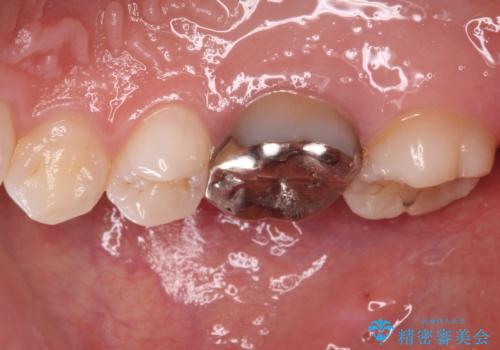

- 奥歯の銀歯が外れたことをきっかけに、全ての銀歯をセラミックに替えたいとのことで来院された患者様です。

第一大臼歯4本と、メタルインレーが装着されている2歯をセラミッククラウンならびにセラミックインレーにて補綴治療・修復治療を行うこととしました。